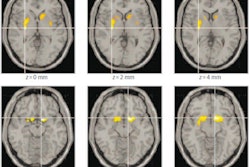

A group of researchers led by Dr. Rashmin Achalia of Government Medical College in Aurangabad, India, found that a machine-learning algorithm achieved the highest accuracy for bipolar disorder when it took into account neuroimaging -- structural MRI, resting-state functional MRI, and diffusion tensor imaging (DTI) -- along with neuropsychological test results.

The participants all received structural MRI, resting-state functional MRI, and DTI on a 1.5-tesla scanner. In addition, they were all given neuropsychological tests by an experienced clinical psychologist in order to assess executive functioning.